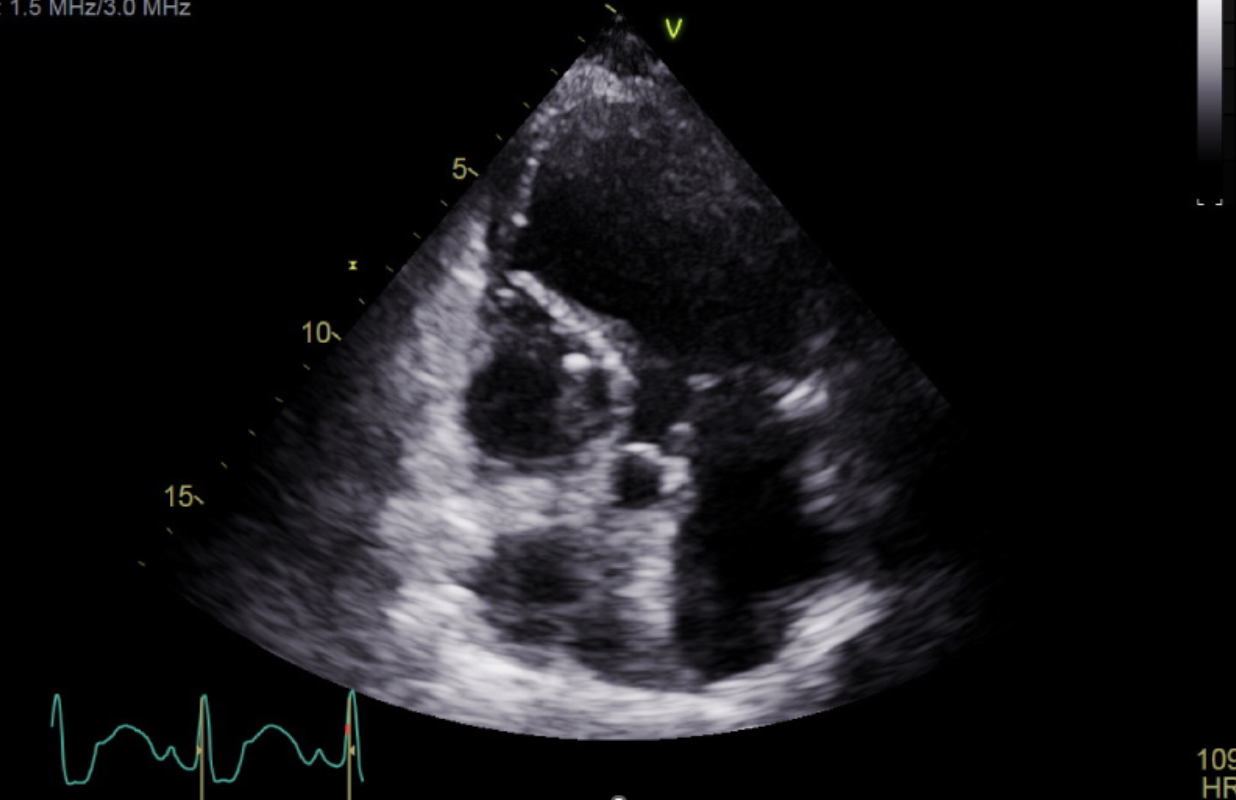

ECG showed tachycardia with new anterolateral Q waves and ST elevation in V2–V5, prompting STEMI activation. Bedside echo showed apical and inferoseptal akinesis. Coronary angiography was deferred due to delayed presentation and down-trending high-sensitivity troponin (618 ng/L). She was admitted to the CCU, where shock improved with norepinephrine, milrinone, and IV diuresis.

Her course was complicated by new-onset atrial fibrillation with RVR. Despite IV amiodarone, RVR persisted, along with worsening respiratory status and increasing vasopressors needs. Limited echocardiography revealed basal hypercontractility and dynamic LV outflow tract obstruction (LVOTO). Esmolol was considered to reduce the gradient. Simultaneously, pulmonary artery catheter readings suggested new left-to-right shunting. A new loud holosystolic murmur was heard, and repeat echocardiogram confirmed a large ventricular septal rupture (VSR).